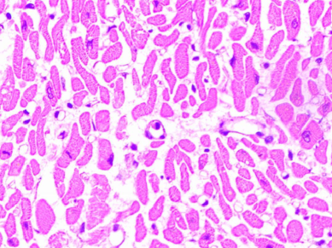

High Quality Image

Outstanding image quality for various sample types including Histopathology, Cytology, PBS etc

Achieve high quality images of resolution up to 0.19 μm/pix at true 40x

We've used Micalys by Medprime for our inter-hospital Senior Surgical Meetings for 2 years (2021-22). The program digitized 18 case slides, with excellent color reproduction, clarity, and resolution. The cytoplasmic/nuclear details were also impressive. We had no trouble offering diagnoses, and the program was easy to use and highly recommendable.

Our laboratory has been using Micalys, developed by MedPrime, for the past 2 years. Using this device, we have remotely diagnosed over 43,800 cases approx in these 2 years. To evaluate the performance of Micalys, we compared it with manual microscopy using 60 slides and three pathologists. We found no significant difference in the interpretation of diagnoses using both methods except for those that resulted from human subjectivity. The images produced by Micalys are as clear and detailed as those produced by conventional microscopy, even at maximum magnification. The colors are reproduced accurately, and the nuclear details are sharp.

Dr Chandralekha TampiMD-Pathology. Consultant Histopathologist, Lilavati Hospital and Research Centre, Mumbai

We hosted two Histopathology academic meetings with over 100 histopathologists from Mumbai's government, private teaching, and referral hospitals. Through Micalys, we uploaded challenging cases' scanned and high-quality images for detailed diagnostic viewing. The images were consistently of excellent resolution with crisp details and faithful color reproduction. All participants found the images to be of superior quality. Kudos to the team for this high-quality product.